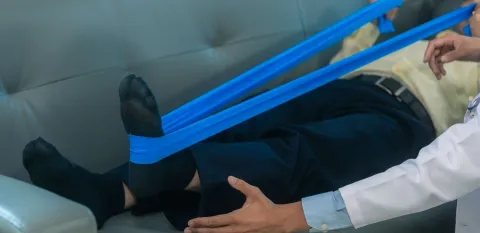

7 Steps to Healthier Joints

These seven steps will help preserve the cartilage you have, strengthen the muscles that support your joints, and help you live with greater mobility and less pain.